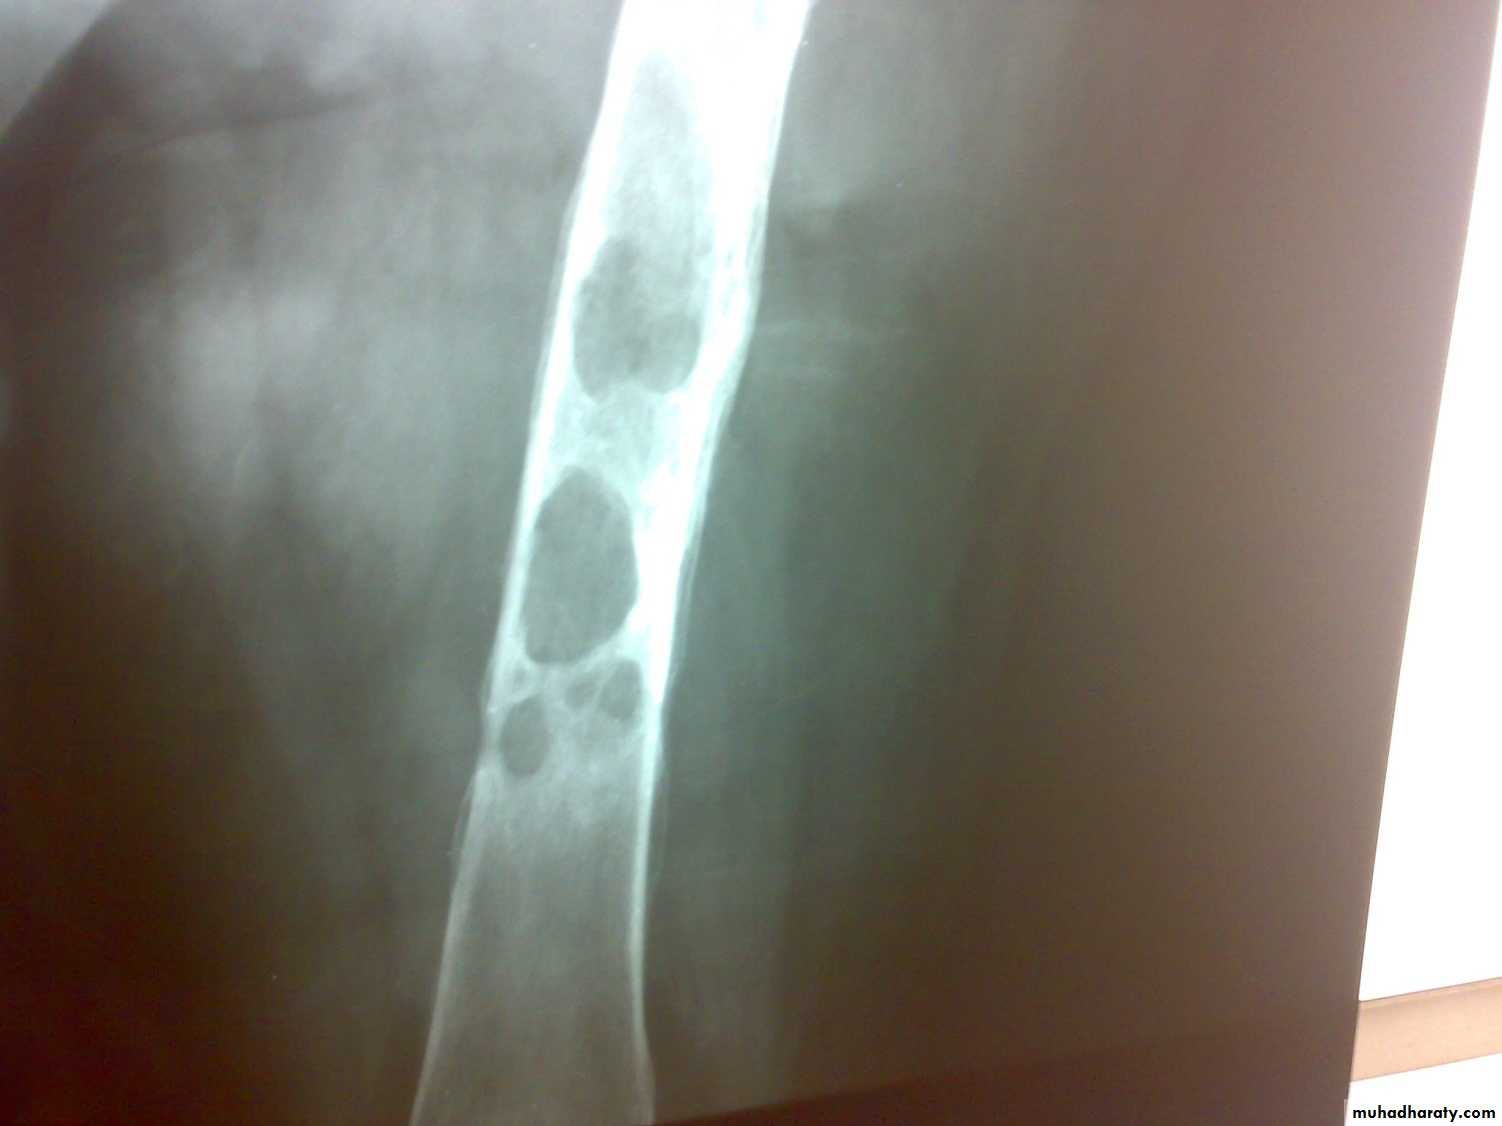

Radiological features

early changes:

Soft tissue swelling, Periarticular osteoporosis

Loclized osteoprosis (Bone ends ‘washed – out’ or localized decalcification ).

Narrowing and irregularity of the articular ends.

Late changes:

Erosions of the subarticular cartilage.

cystic changes appeared.

T B spondylitis may appear as localized bone erosion and collapse across an intervertebral disc space

There may be soft tissue traces of paravertebral abscess.